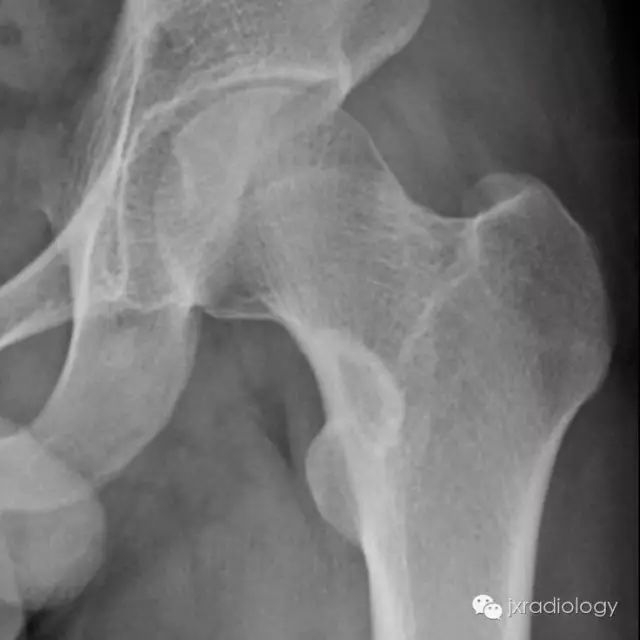

X线检查示骨纤维异常增殖症(Fibrous dysplasia ,FD)病变位于髓腔内,多见于骨干,病变区域多透亮,很少情况下出现高密度影(基质钙沉积时可出现),正常的骨小梁结构消失,代之以细颗粒“毛玻璃”样,有时病变周围的硬化骨带则可组成“果皮征”(rind sign)。

图示